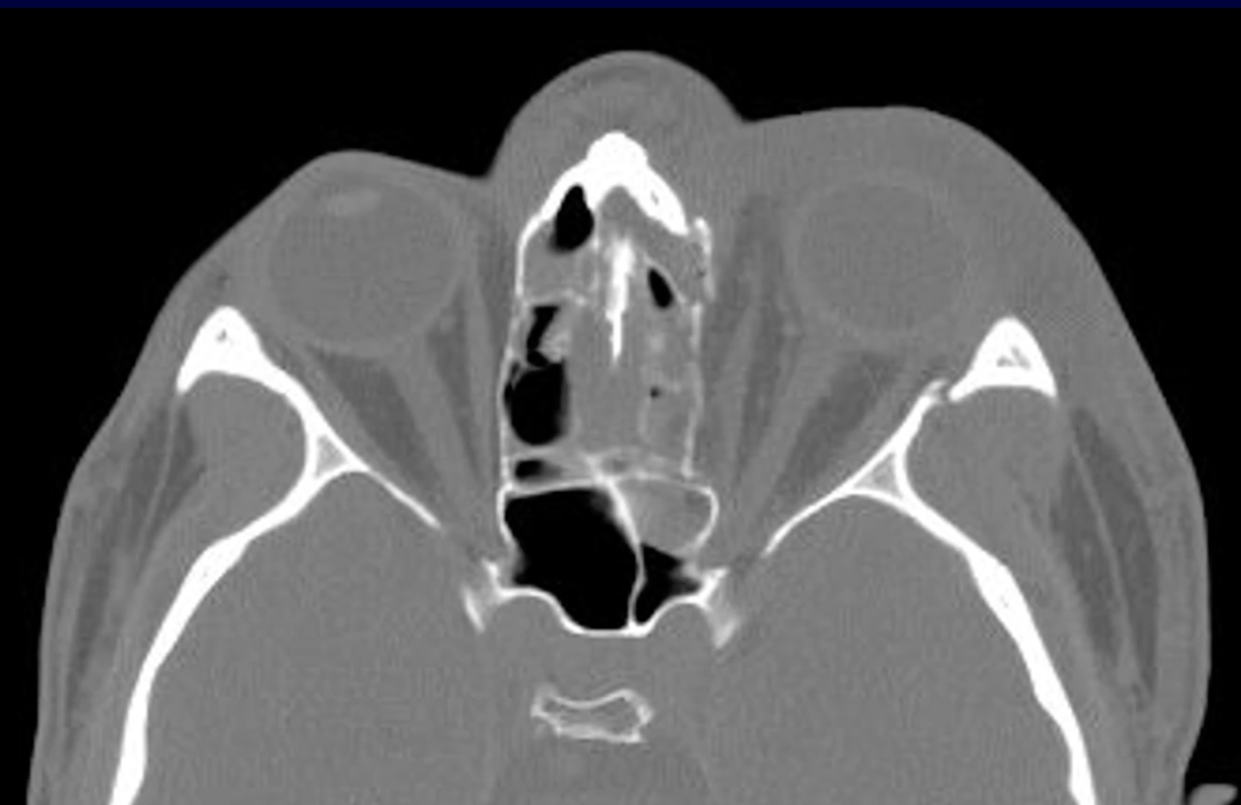

47M presents with multiple facial injuries following high impact car accident where he slammed the side of his chin/face into steering wheel. Endorses malocclusion. CT max face shows medial displacement of condyle.

Where does he most likely have fractures? In what order should they be repaired and how?

R condylar neck fx and L mandibular body or parasymphysis fx

First, you place pt in pre-morbid occlusion with arch bars and MMF. Then, you repair fx's within dental arch, moving anterior to posterior to guarantee proper occlusion. At the end, you reduce edentulous fractures (ie. condyle)

Can use 1 monocortical mini plate (2.0mm) per fracture making sure to have 3 holes on each side.

**studies no longer support needing rigid fixation of one of the fractures (with 2 mini plates, locking plate or 2.0 recon plate) - https://pubmed.ncbi.nlm.nih.gov/37772893/

Then you can treat the condylar neck fracture with MMF for 2 weeks or fixate it with 1-2x 2.0mm miniplates depending on height of fx.